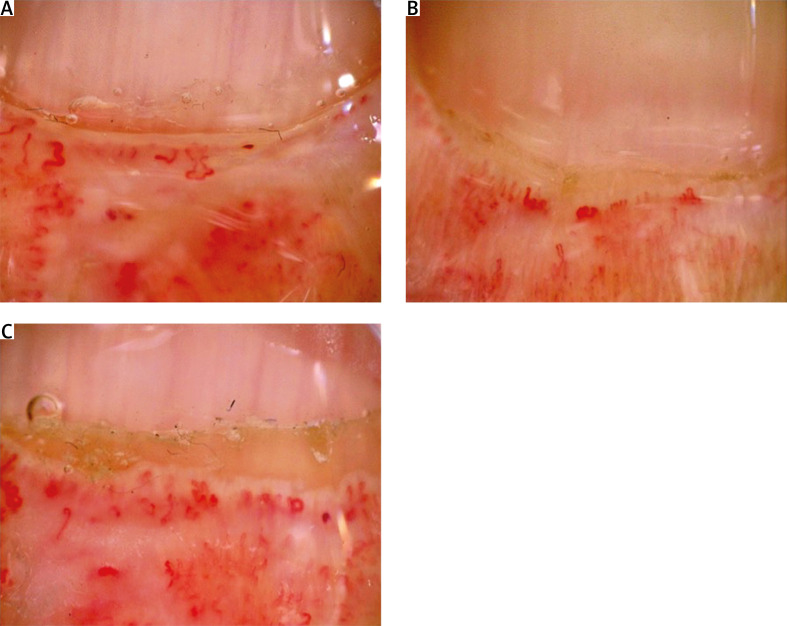

Chronic intestinal pseudo-obstruction (CIPO) is an infrequent and menacing complication of systemic sclerosis (SSc). While researchers report positive impact of rituximab (RTX) on CIPO in paraneoplastic syndrome, no case reports exist for SSc-associated CIPO. The aim of this case-based review is to analyses current literature in context of particular CIPO case description. This analysis was based on PubMed/MEDLINE database and was conducted using the selected key terms. Finally 40 studies/case reports and one case description from authors clinical experience were included into comparison and discussion. As conclusion description of successfuly treatment with RTX and intravenous immunoglobulins can confirm the suggestions from other studies that B-cells participate in the pathogenesis of SSc, making RTX a potentially effective therapeutic option also in coexisting CIPO.